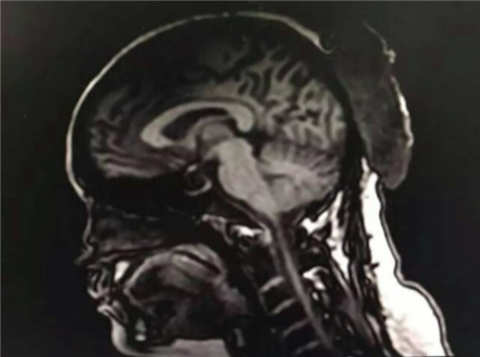

败血症又称脓毒血症,是由于细菌或者病毒侵入血循环,并在血液中生长繁殖,产生毒素而发生的急性全身感染。医生说,从鼻子、嘴唇到下巴,是典型的“危险三角区”,毛细血管密集。喻先生将痘痘挤破以后,细菌从毛细血管侵入,从而引起严重感染。目前,喻先生仍然在调节当中。